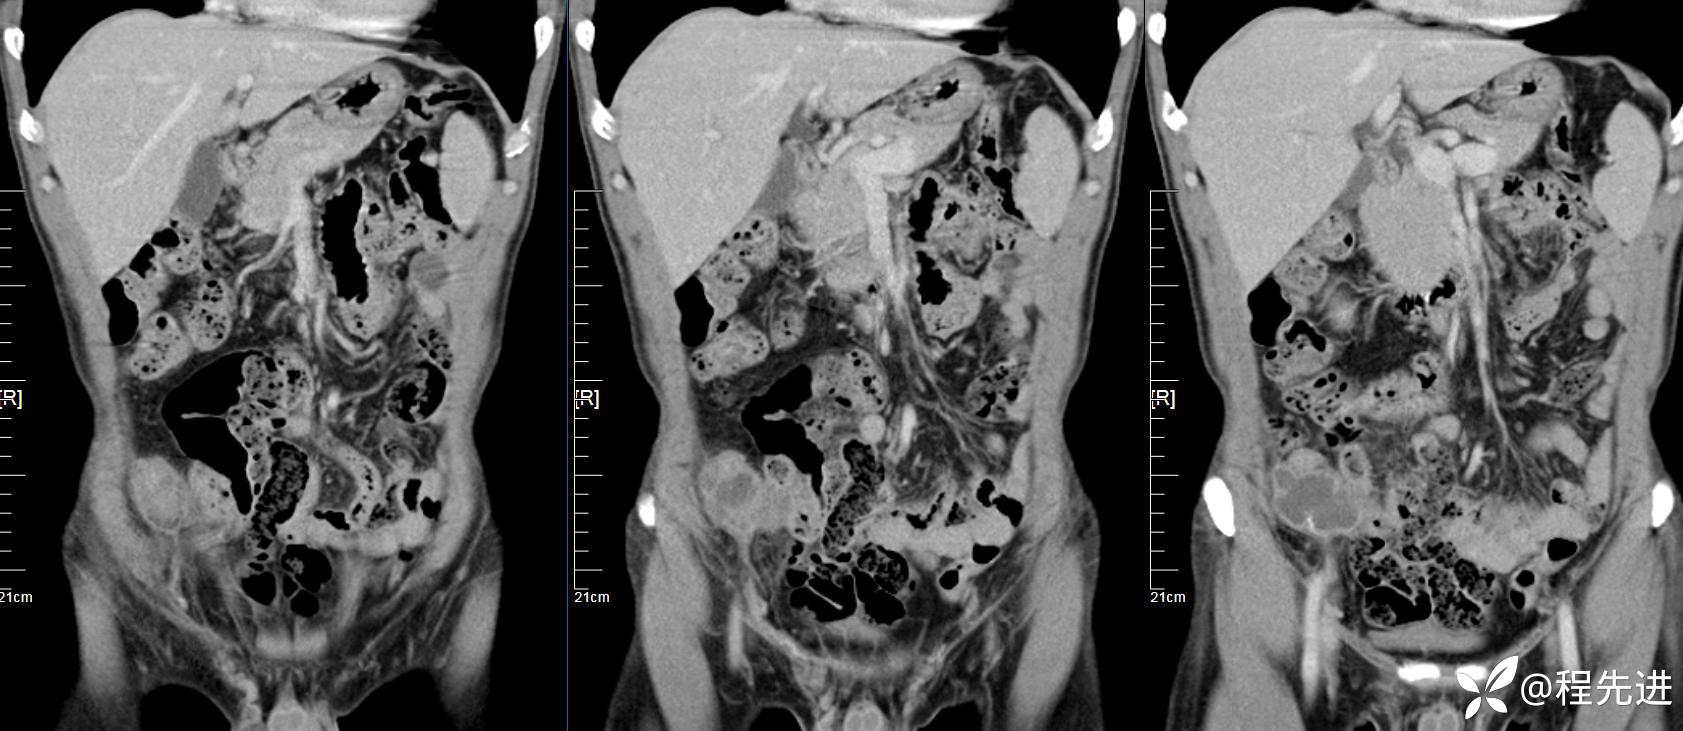

【患者信息】:男,61岁

【现病史及既往史】:右下腹部疼痛伴腹胀2天

【影像检查】